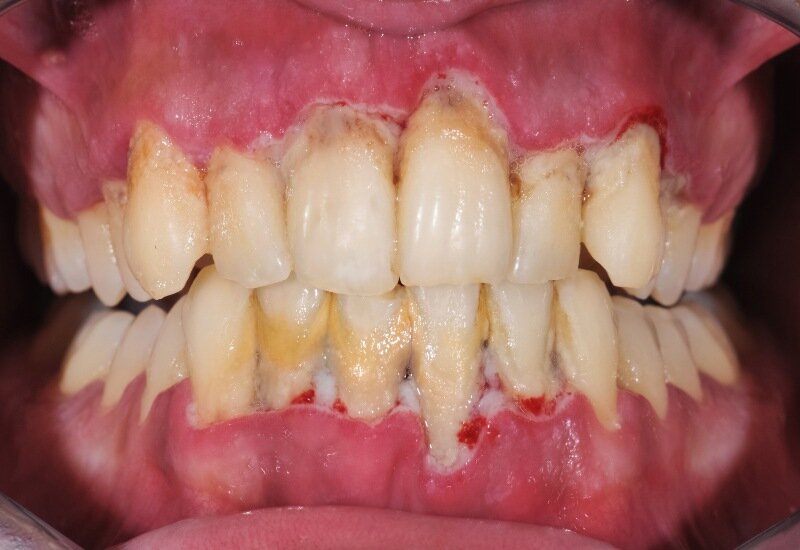

اگر ژنژیویت درمان نشود و پیشرفت کند به پریودنتیت تبدیل میشود. پریودنتیت در درجه اول ناشی از تجمع پلاک، یک لایه چسبنده از باکتریها است که روی دندانها تشکیل میشود. هنگامی که پلاک به طور منظم برداشته نشود، میتواند به جرم تبدیل شود که میتواند لثهها را تحریک کرده و منجر به التهاب شود. پیشرفت این بیماری باعث میشود که لثهها از دندانها جدا میشوند (عقبنشینی لثهها) و بافت زیرین نگهدارنده دندانها آسیب میبینند. این بیماری در ادامه میتوان به از دست دادن دندانها بینجامد.

پریودنتیت میتواند قرمزی، تورم یا خونریزی لثه، لقی دندان، بوی بد دهان مداوم، درد یا حساسیت هنگام جویدن و چرک بین دندانها و لثهها بینجامد.